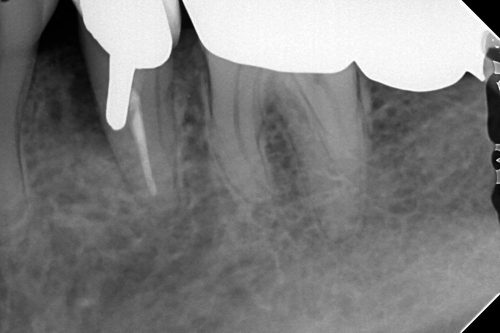

パーフォレーション(誤ったところに穴が開けられた症例)のリペア

このように根尖に病変がないのに、病気が出来てしまうケースがあります。

この症例はメタルコアを形成するときに間違って根管内に穴を空けられてしまったようです。